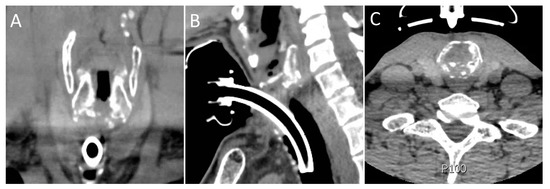

Figure 2.

Preoperative coronal (A), sagittal (B), and axial (C) images of patient “A”. Note diffuse sclerosis and destruction of the posterior cricoid plate.

The indication for T-tube placement, as opposed to open resection, in 4 of the 5 (80%) cases was the proximity of stenosis to the vocal folds, combined with sclerosis of the cricoid in 2 of these cases, as well (Figure 2). In the fifth patient, there was concern about patient tolerance of open resection and recovery due to significant cardiac pathology and poor pulmonary status. Two patients (40%) had significant cardiac disease, and one of these patients also had poorly controlled type 2 diabetes mellitus. No patients had an autoimmune disease. The median ASA classification score was three (Table 1).